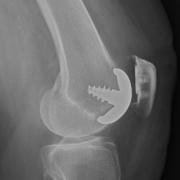

Hemicap patellofemoral replacement from the side

A metal component replaces the damaged trochlear groove of the femur, and a plastic button replaces the rear patellar surface which is cut away to accommodate the implant.

The trochlear implant is comprised of metal and shows up as white. The plastic patellar component is showing only as a space between the trochlear implant and the remainder of the patella.